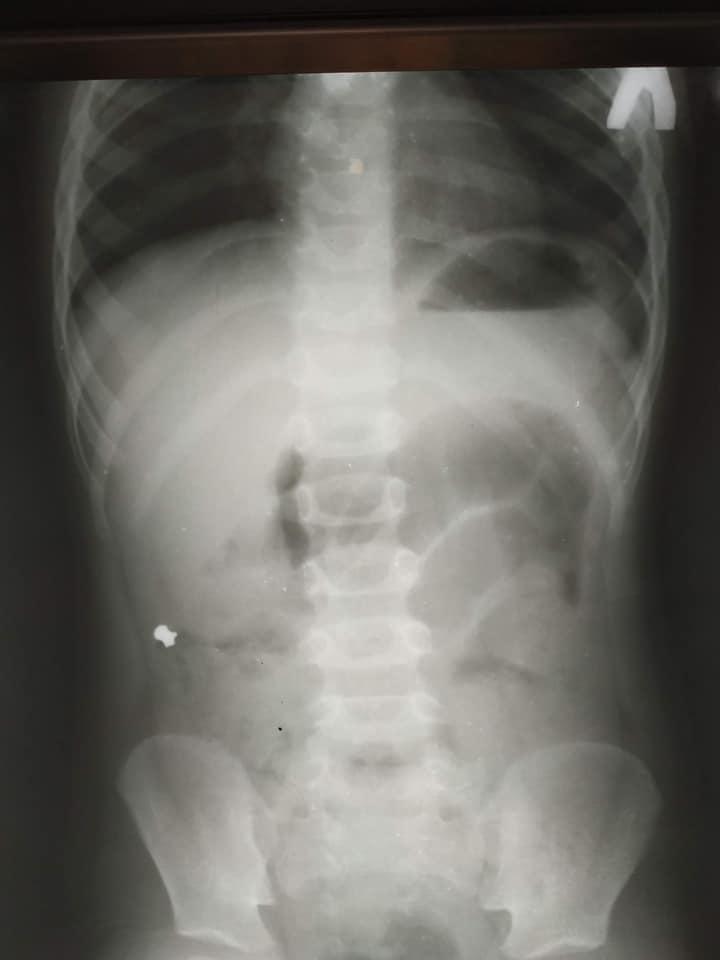

Дитячого хірурга Кирила Лапшина дуже здивував рентген-знімок. У черевній порожнині чітко візуалізувався дивний сторонній предмет, який за обрисами схожий на кулю від пневматичної гвинтівки.

Медик уточнив у тата хлопчика, чи міг син проковтнути кулю. Чоловік повідомив, що у них вдома є пневматична рушниця та до неї металеві кулі, якими дитина нещодавно гралася. Ймовірно, випадково хлопчик проковтнув одну з них. Все б закінчилося добре, якби куля потрапила зі шлунка в кишківник і вийшла.

Але в маленького пацієнта куля потрапила в апендикс, це стало причиною запального процесу, через що хлопчику знадобилася термінова операція.

Хворому провели лапароскопічну операцію — видалили запалений апендикс через три невеликі проколи у животі.

«Коли ми видаляли апендикс, я відразу побачив, що в ньому є потовщення. Ми його видалили й уже назовні розрізали. Там справді була куля! Вона, як стороннє тіло, потрапила з кишківника в апендикс і створила його обструкцію. Це і стало незвичайною причиною апендициту», — повідомив дитячий хірург Кирило Лапшин.